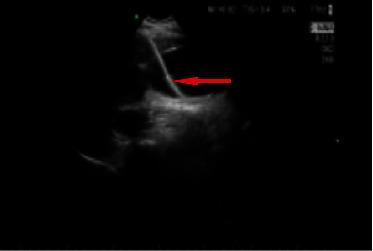

Ultrasound-Guided Percutaneous Transhepatic Gallbladder Drainage Improves the Prognosis of Patients with Severe Acute Cholecystitis.

The aim of this study was to investigate the clinical efficacy of ultrasound-guided percutaneous transhepatic gallbladder drainage (PTGD) for the treatment of severe acute cholecystitis (AC). The data of 40 patients diagnosed with severe AC at our hospital between August 2020 and June 2021 were retrieved and classified into a PTGD group, open cholecystostomy (OC) group, laparoscopic cholecystectomy (LC) group, and conventional conservative treatment (CT) group. Before treatment and on days 1, 3, 5, and 7 after treatment, their serum levels of alanine aminotransferase (ALT), alkaline phosphatase (ALP), aspartate aminotransferase (AST), total bilirubin (TBIL), triglyceride (TG), high-density lipoprotein (HDL), low-density lipoprotein (LDL), white blood cell count (WBC), IL-2, IL-4, IL-6, IL-8, and cancer antigen 19-9 (CA19-9) were measured. Additionally, clinical manifestations such as body temperature and pain score were monitored before treatment and at 24, 48, and 72 hours after treatment. The recovery time and complications/adverse reactions were statistically analyzed, and the Kaplan-Meier survival curve was plotted. After treatment, compared with the other three groups, the PTGD group had a significant reduction in serum indicators, including WBC and inflammatory factors, recovery time, pain score, and complications, and benefitted from better treatment efficacy and higher survival rate. Thus, ultrasound-guided PTGD was found to be more effective in treating severe AC patients and was associated with improved patient prognoses.